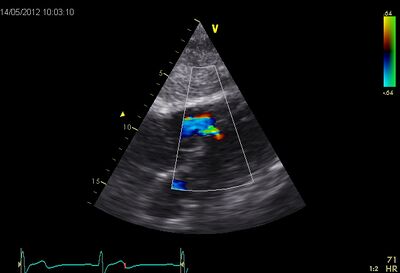

VSD.jpg VSD02.jpg

Muscular VSD tilted by PLAX Muscular VSD Subcostal 4CH